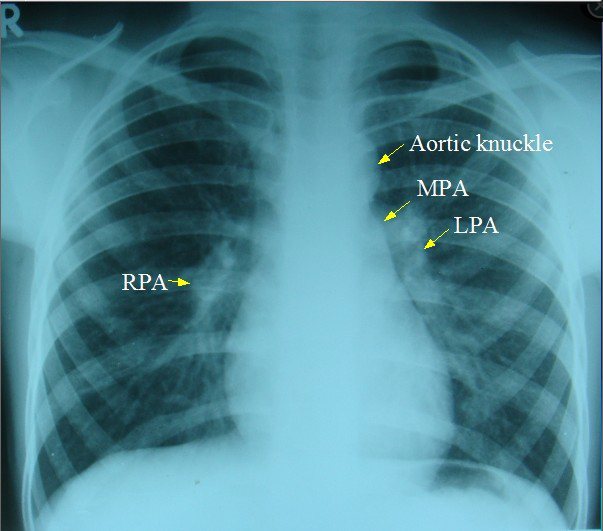

Perfusion 101 If you were wondering what a perfusionist is, basically it can be summed up as “we stop your heart to keep you alive”, an almost paradoxical statement for a profession so few realize even exists. As the title on the cover says, this is a book on open heart surgery in America, and…